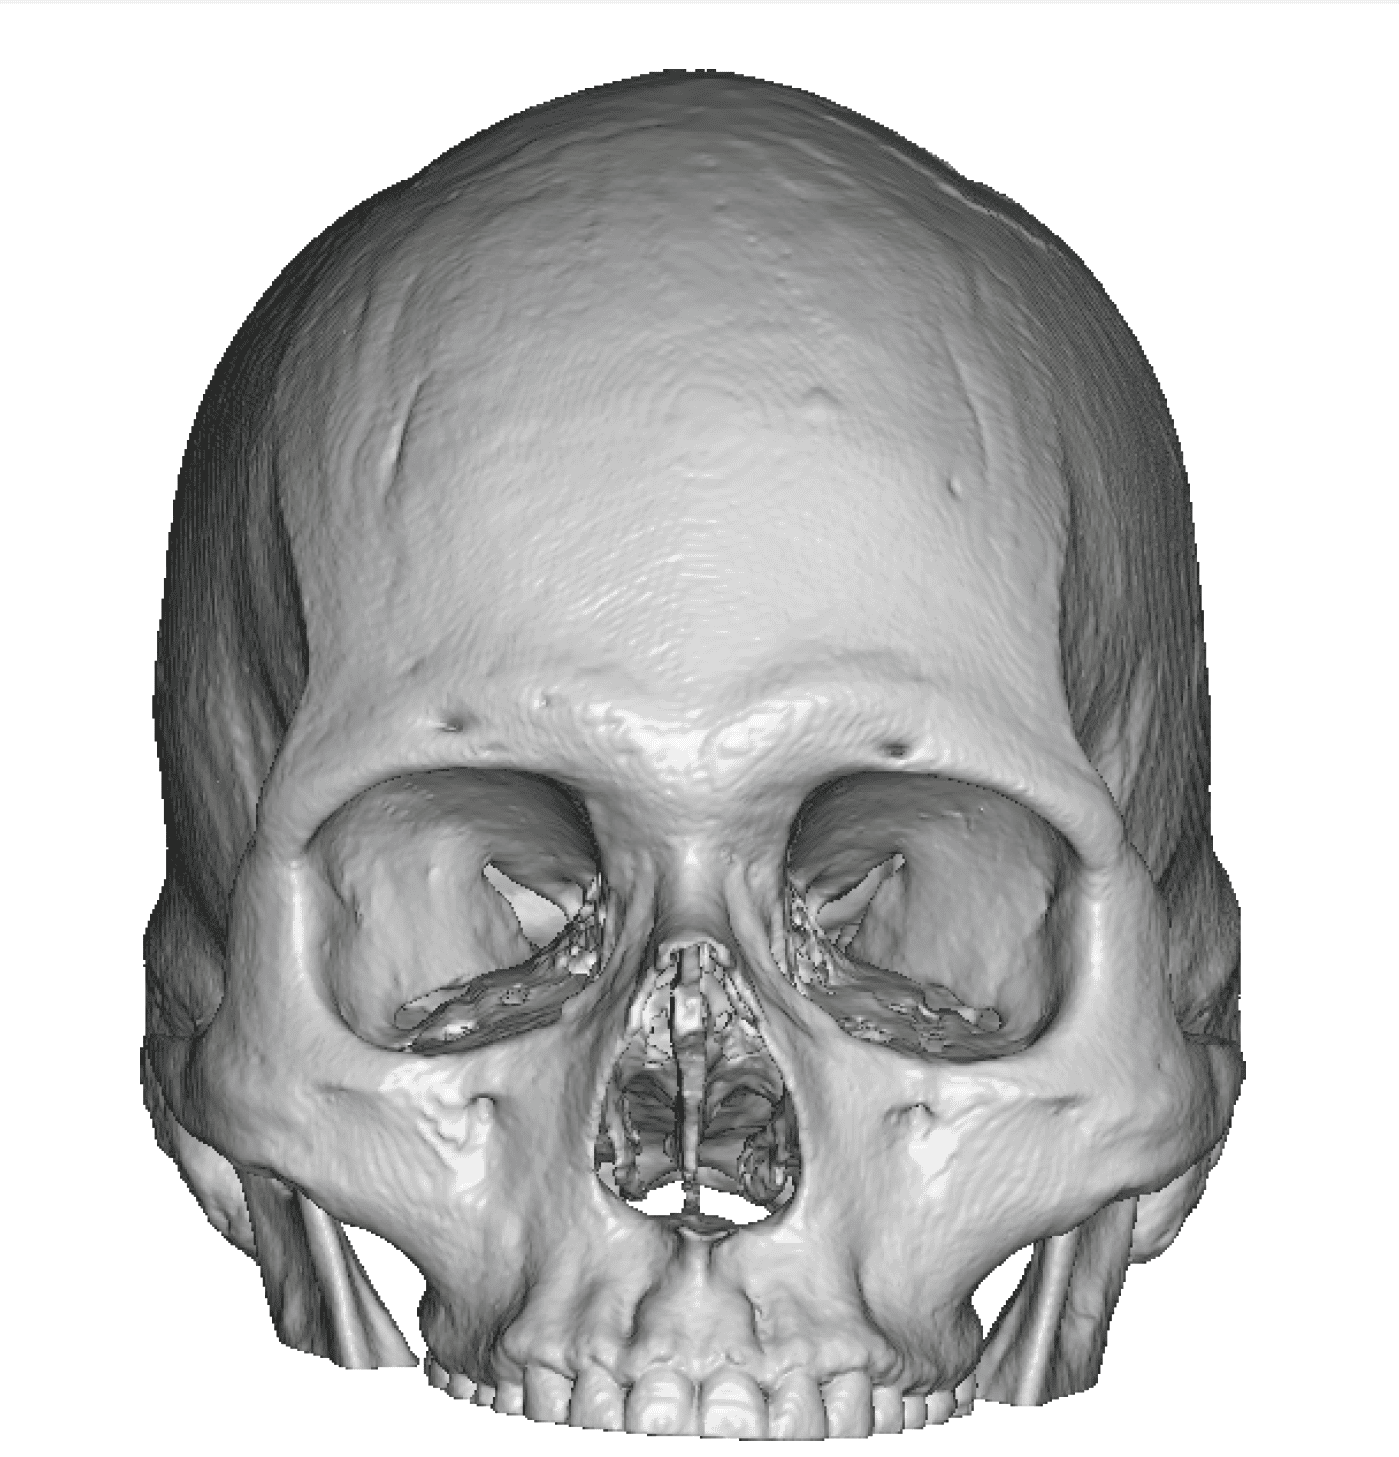

Patient 28

Desire for rounder shape to the top of the head from a congenital parasagittal deficiency skull shape.

Custom skull implant designed to fill in the parasagittal deficiencies.

Desire for rounder shape to the top of the head from a congenital parasagittal deficiency skull shape.

Custom skull implant designed to fill in the parasagittal deficiencies.